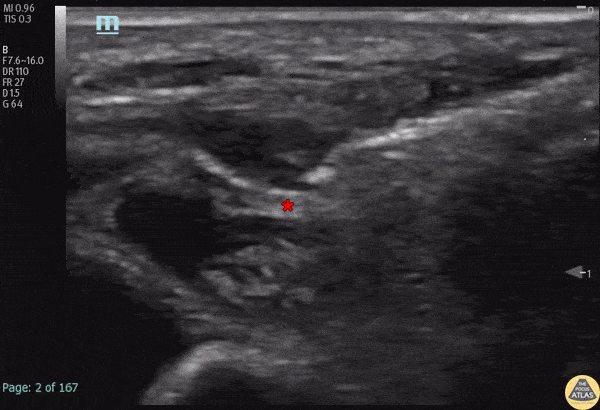

A 50 day-old male was transferred from an outside hospital with concern for NAT after skeletal survey showed old rib fractures, and a significantly displaced and angulated femoral midshaft fracture. A ultrasound-guided fascia iliaca block was performed to aid with passive reduction while in a Pavlik harness. Anesthetic spread can be seen along the fascial plane just superior to the femoral nerve (*). The pulsating femoral artery is seen medial (left of screen) to the nerve. The patient had pain relief with the block, and follow up radiographs showed better reduction after being in the harness without manual manipulation. Dr. Michael Heffler, PGY3, Denver Health Residency in Emergency Medicine Dr. Emily Greenwald, 3rd year PEM fellow, Children’s Hospital Colorado Dr. Megan Mickley, PEM Attending Physician, co-director Pediatric Emergency Ultrasound, Children’s Hospital Colorado